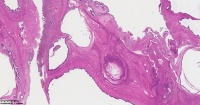

炎性息肉?潴留囊肿?腺体是否有问题?

性别

女

年龄

51岁

临床诊断

一般病史

宫颈赘生物

标本名称

图4

息肉。

稳妥起见最好做一做免疫组化。